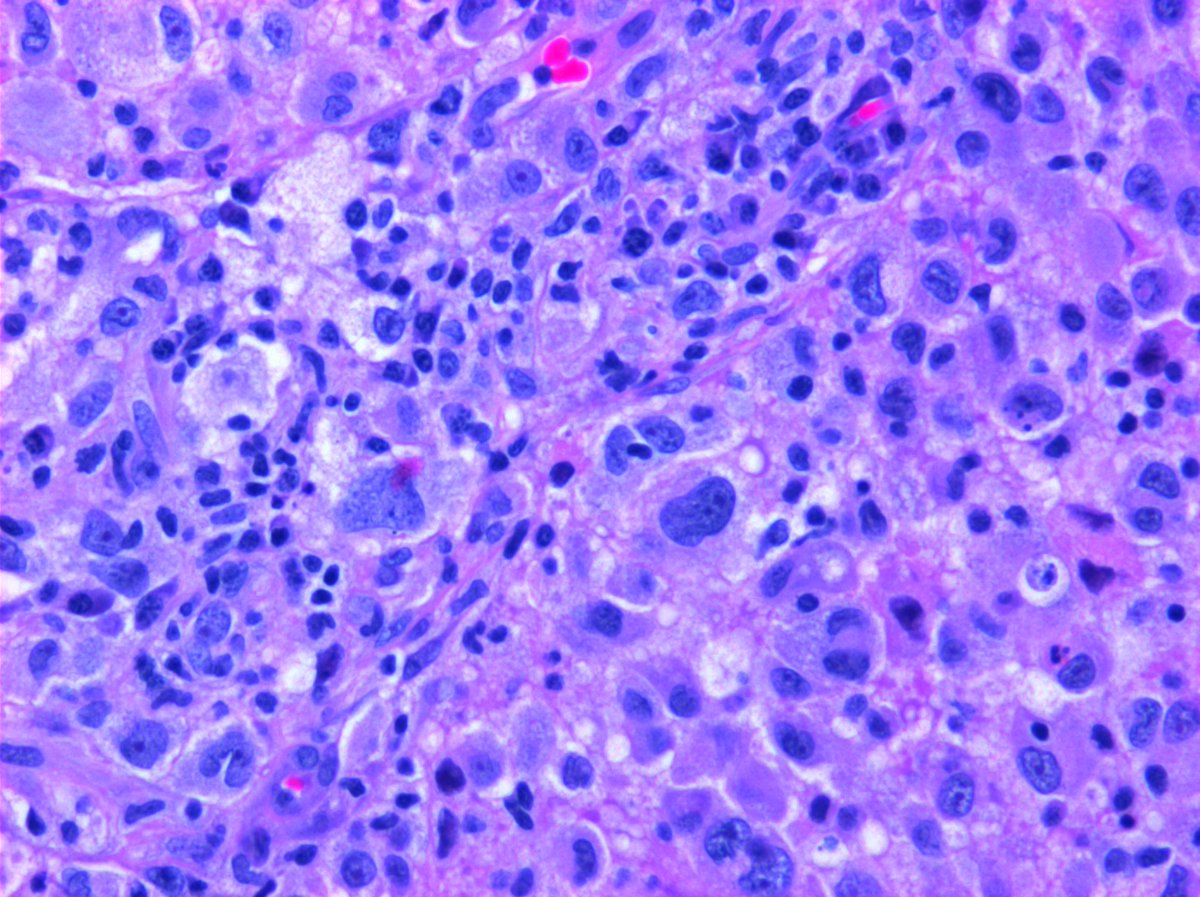

#Pathresidents: Let’s take a look at two biopsy cores (from the same patient) and decide what to call them.

Take a look at both cases (“A” in this post, “B” in reply). Cast your vote. Then, read on for some teaching points geared towards trainees and general fans of #GUPath.